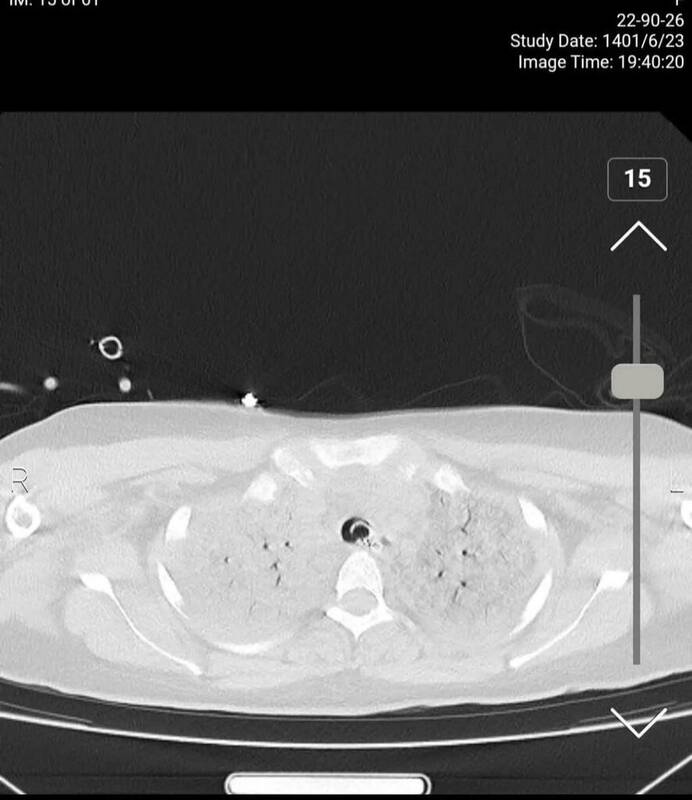

برای بررسی وضعیت ریه بیمار نیز با تخصص رادیولوژی گفتوگو کردیم که وی توضیح میدهد: در سیتیاسکن ریه شواهد کانتیوژن یا له شدگی بافت ریه مشاهده میشود که پس از «سی پی آر» رخ میدهد و ممکن است در هر بیماری رخ دهد و این موضوع غیرطبیعی نیست.